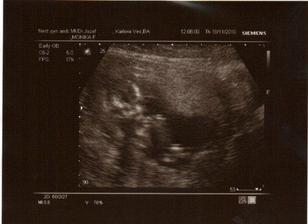

✿♥♥♥♥Bude to dievčatko!!!!! ♥♥♥♥✿

Bude to Stella 🙂

krasne 3D sono 🙂